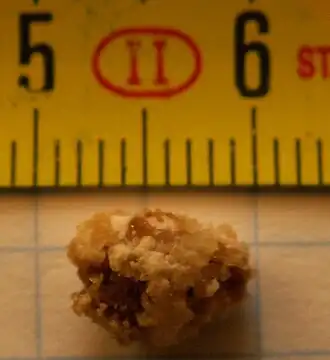

| Cálculo renal com 8 mm de diâmetro | |